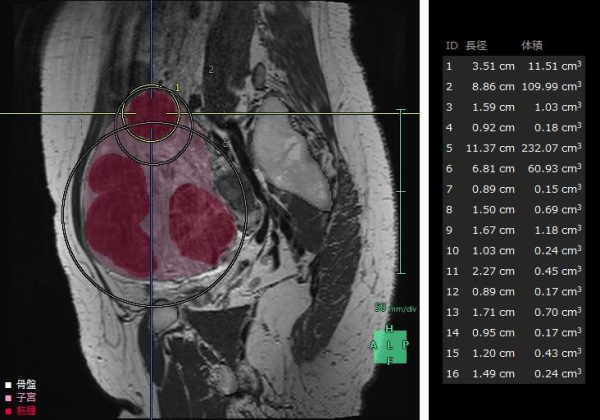

子宮筋腫は、成人女性の罹患率が20~30%と高頻度に見られる疾患で、機能温存が重要とされている。MRIや超音波画像診断装置の2D画像では筋腫や周囲組織の3次元的な把握が難しく、骨盤内の複雑な解剖構造の理解も困難である。また、筋腫の大きさや数、妊孕性温存の希望などにより様々な手技が適用されるが、筋腫の計測や手技の選択は各医師の経験則や感覚に基づいて行われているという課題がある。「婦人科臓器解析」ではMRIのT2画像からAI技術を活用した抽出エンジンを用いて子宮周囲の臓器をセグメンテーションし、ユーザーが子宮筋腫と判断した箇所の体積・数・深さの定量化を行うことができる。また、3Dで周辺組織との位置関係を把握することで筋腫手術の低侵襲化や取り残し防止等への寄与が期待される。

婦人科臓器解析の解析画面